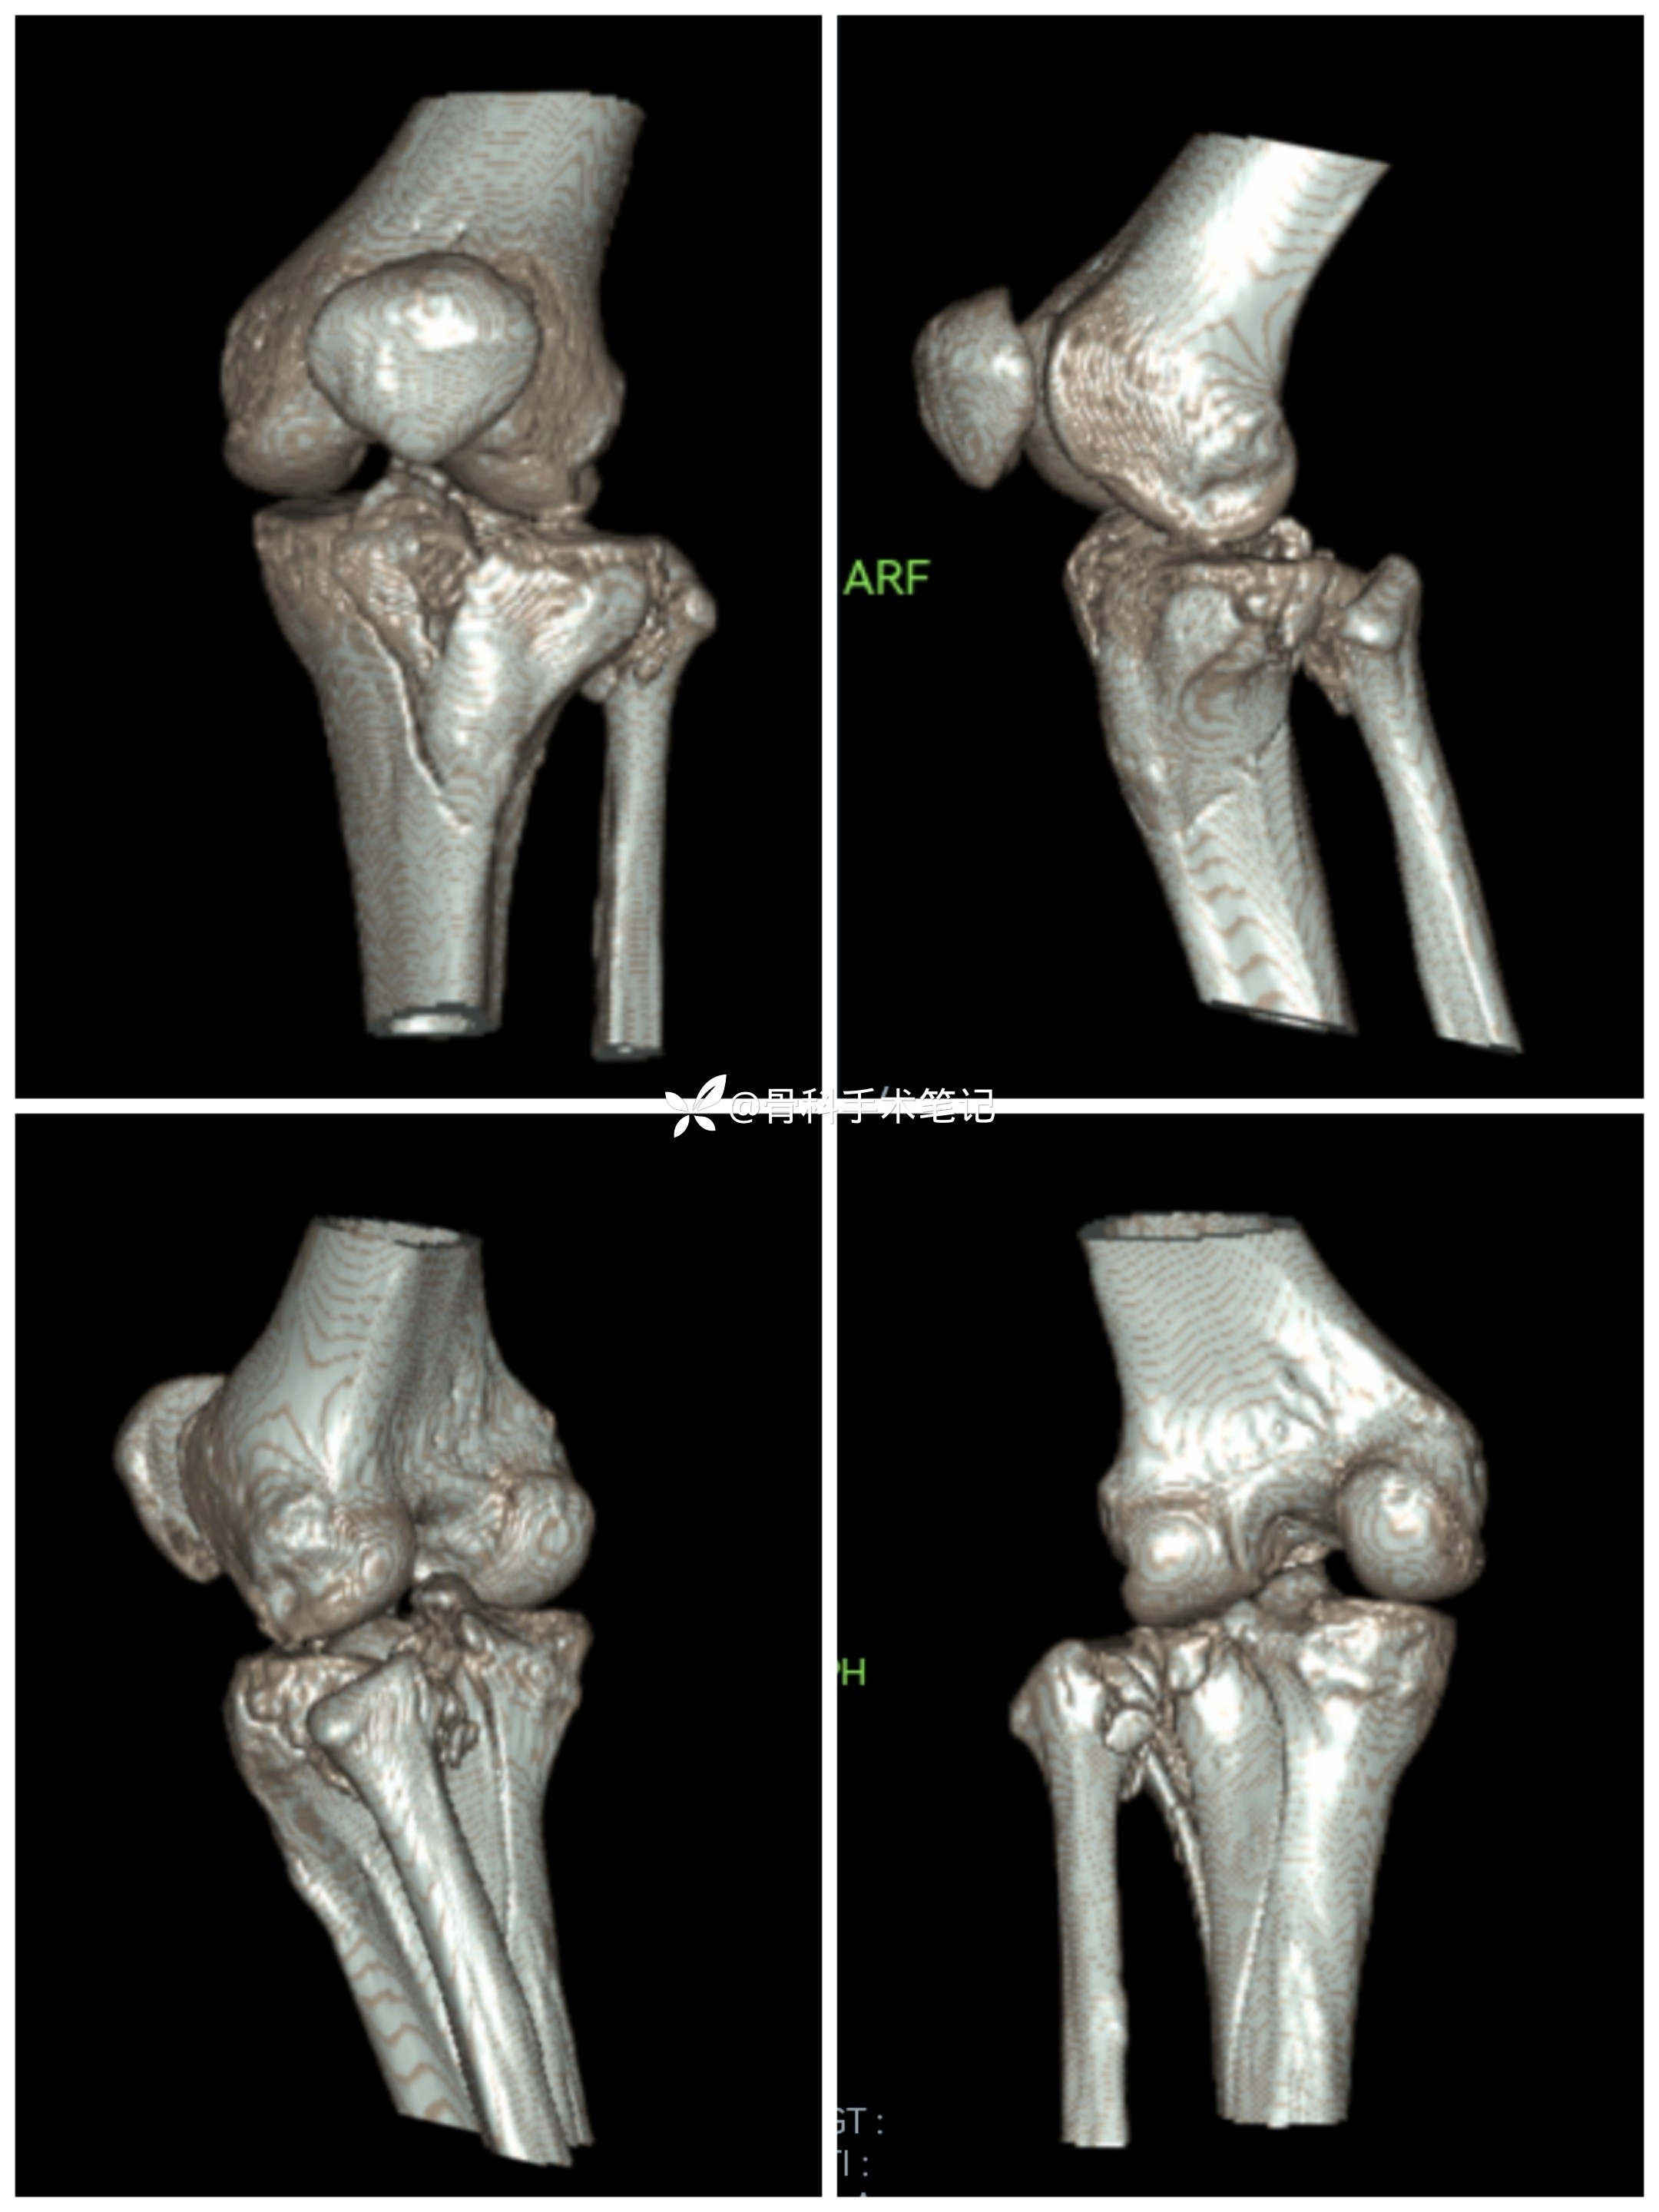

【患者信息】:女,50岁

【主诉】:高坠伤致左膝部疼痛伴活动受限3小时余。

【临床诊断】:1.左胫骨平台粉碎性骨折;2外侧半月板损伤。